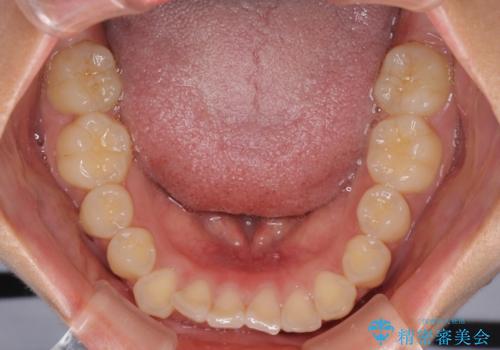

- 上下のデコボコと前歯のクロスバイトを改善したいとのことで来院された患者様です。

極力短期間で治療したいとのことで、ワイヤー装置による矯正治療を行うこととしました。

お住まいが遠方であったため、マウスピースによる矯正治療も提案しましたが、ご自身でのマウスピースの管理の面倒くささと、なるべく早く治療を終えたいとのことで、ワイヤー矯正を選択されました。